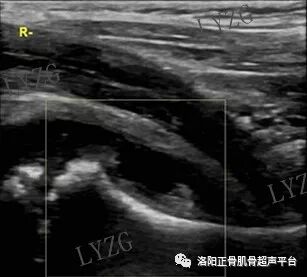

双侧对比,右髋关节前隐窝内团声状中等回声增生滑膜,未见明显积液;左髋关节前隐窝内未见明显积液及滑膜增生

左髋关节前隐窝内积液并滑膜增生(呈条带状)

双侧对比,右髋前隐窝内积液,未见明显滑膜增生;左髋关节前隐窝内未见大于2mm积液,未见明显滑膜增生